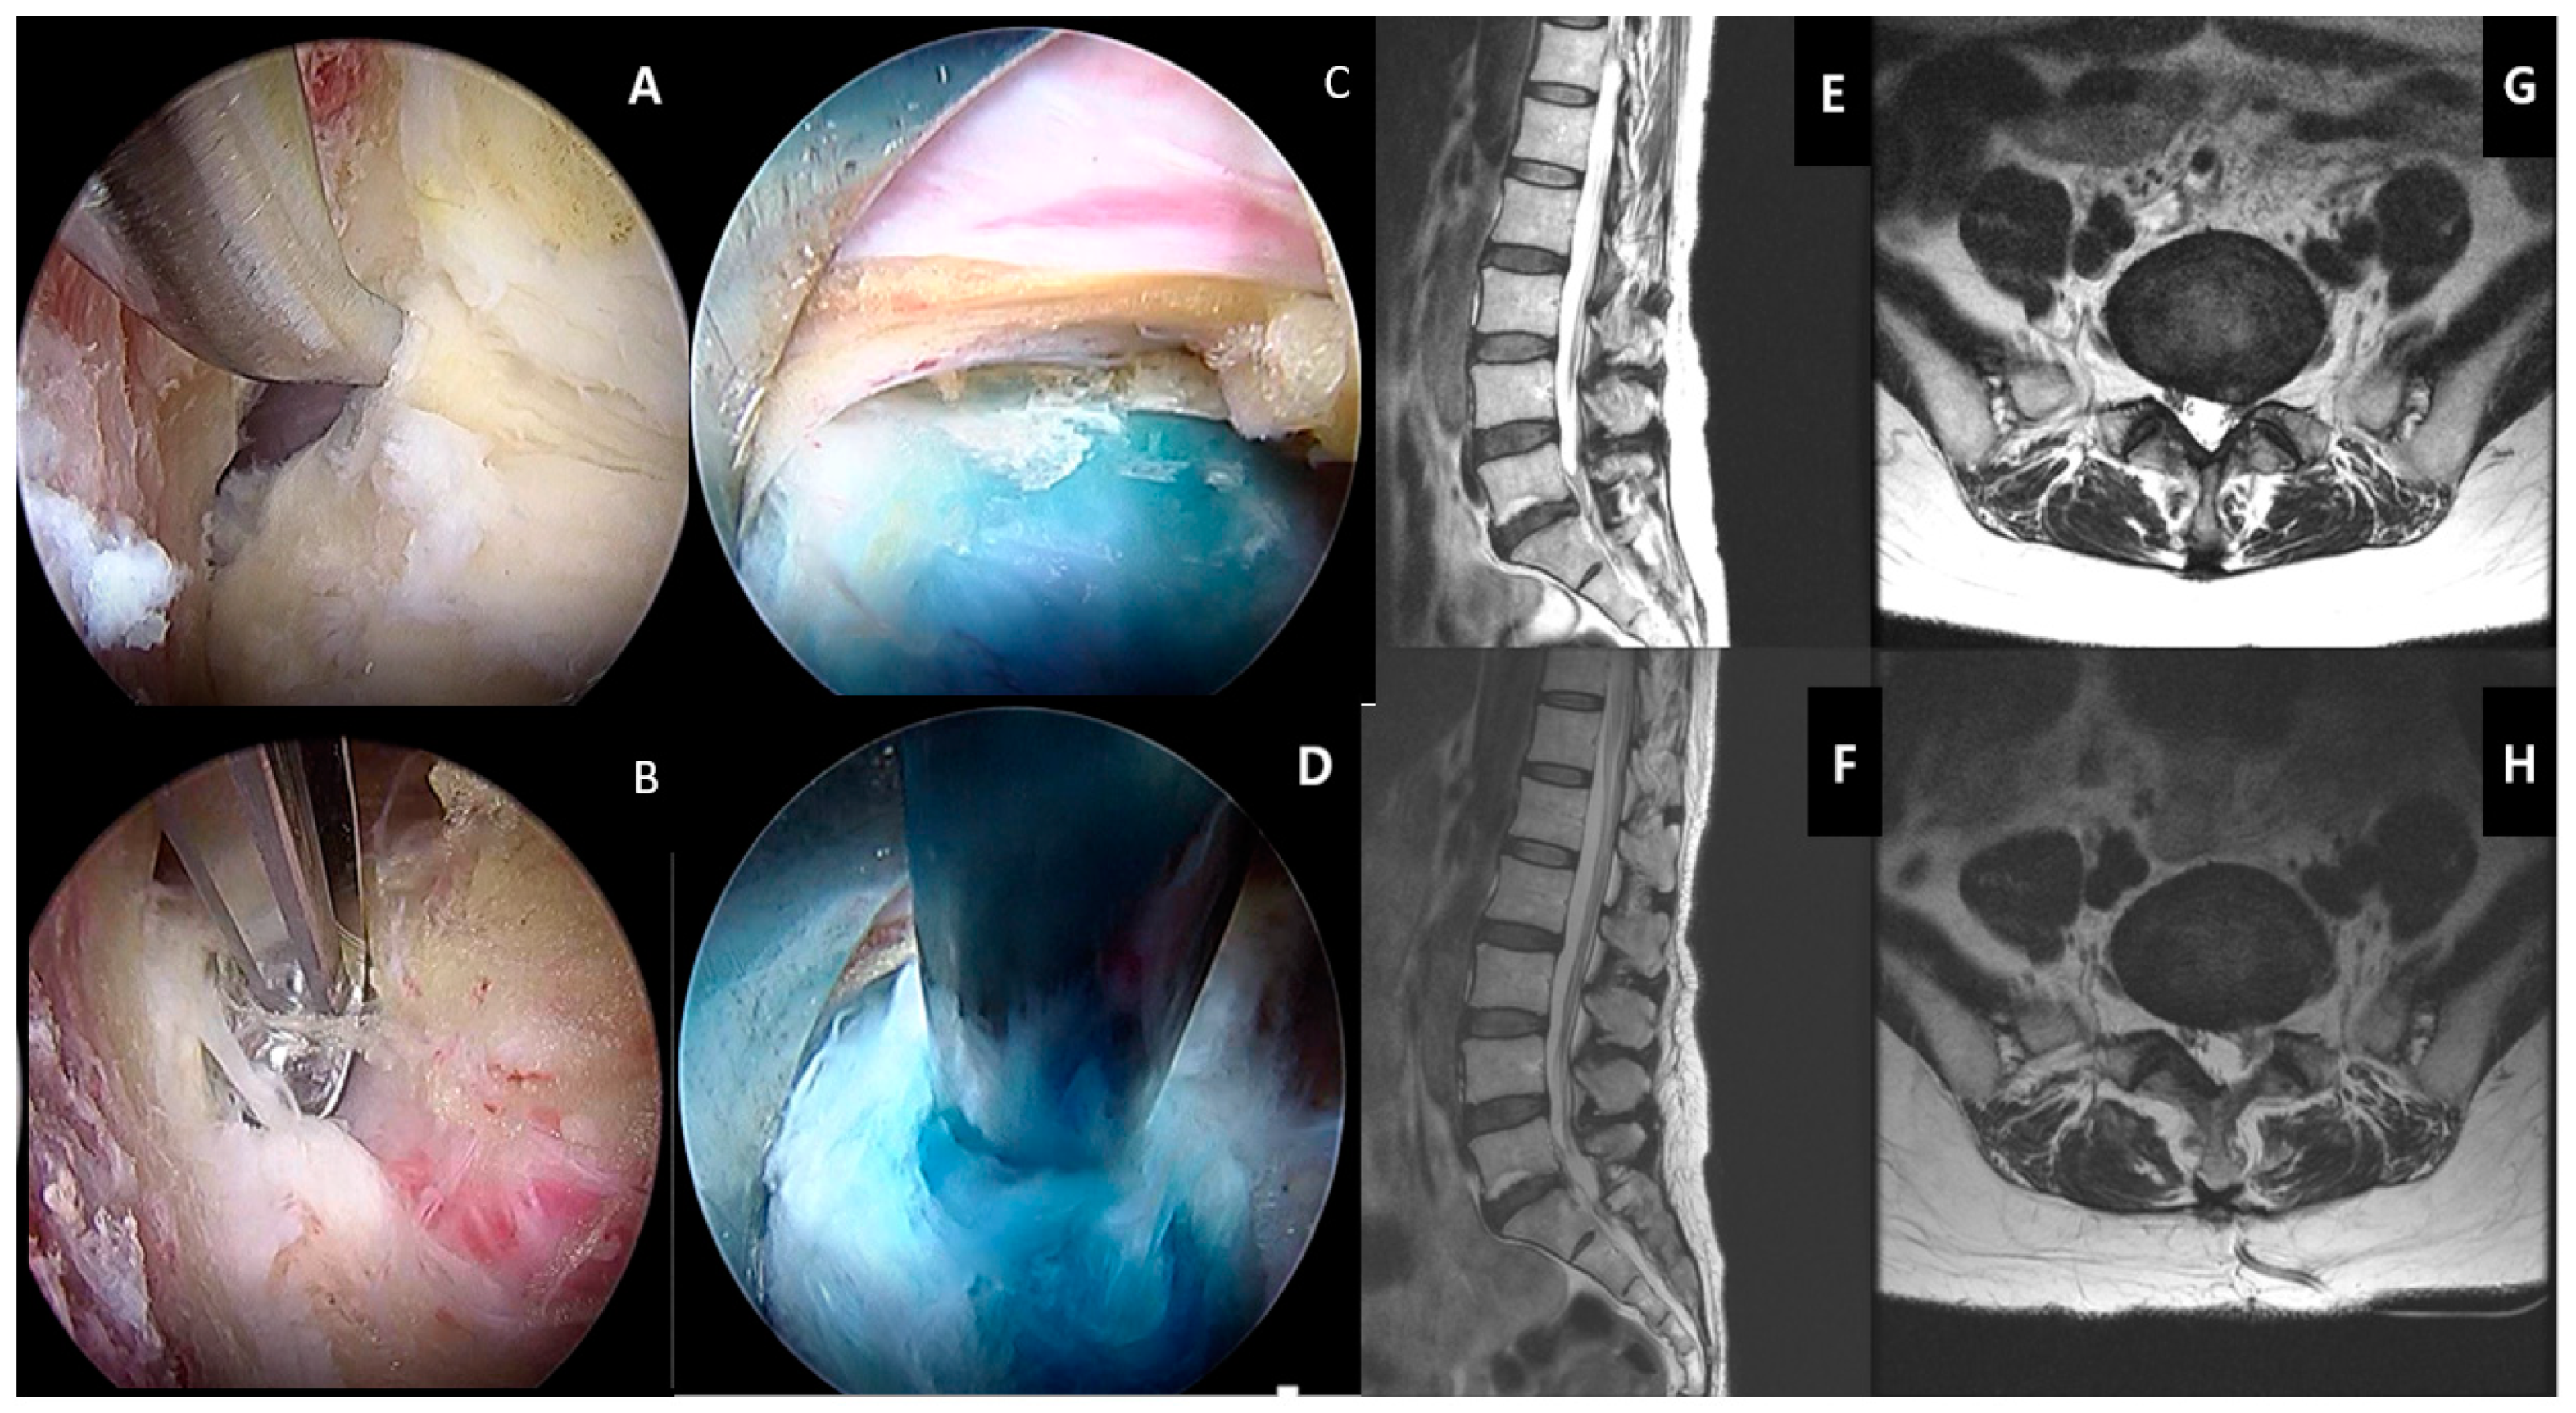

Minimally invasive decompression surgeries can be performed by mini open or tubular retractor with microscopic decompression or the latest technique of endoscopic spinal decompression and discectomy [154,155,156] (Figure 5). With endoscopy, in addition to the posterior and paraspinal transforaminal approach (Figure 5), and a new contralateral approach is available [157,158] [114,159,160]. The long-term outcomes are similar between the open and minimally invasive and endoscopic approach. The soft tissue dissection-wise, endoscopic is least invasive compared to tubular microscopic decompression surgery, which in turn is less invasive than open surgery [161,162].

Figure 5.

Transforaminal endoscopic lumbar discectomy (TELD). Using a beveled-type working cannula with an 8 mm outer diameter. The endoscope is introduced into the surgical field, with the entire procedure performed using constant saline irrigation. A shows the exiting nerve root in view with its surrounding epidural fat tissue. B shows the drilling of the superior articular facet under direct endoscopic vision. C shows the dissection of the foraminal ligament. D showes the exposure of the disc after manipulation of the working channel and endoscope to bring the disc in view. E shows the removal of the disc with endoscopic forceps. F shows the decompressed disc underneath floating neural elements. The blue stain on the disc was caused by indigo carmine disc injection, which served as a colored marker for ease of identification of disc herniation. G shows the herniation of the left L3/4 disc compressing on the neural element in sagittal MRI, which was removed and demonstrated in post-operative MRI of the same level sagittal cut in H. I shows the herniation of the left L3/4 disc compressing on the neural element in the central, paracentral, and foraminal region axial MRI, which was removed and demonstrated in post-operative axial MRI of the same level axial cut in J.